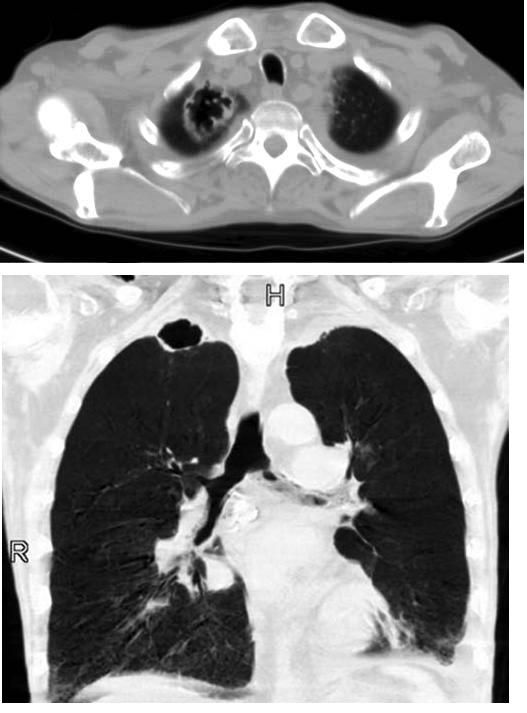

A chest radiograph suggested only scarring in the apex of the right lung (Figure 1); however, a CT scan revealed a thin-walled cavity, measuring approximately 3.9 cm in diameter, with several small adjacent satellite nodules (Figure 2). Acid-fast smears of 3 expectorated sputum samples showed no organisms, and Gram staining showed normal upper respiratory tract flora with a few WBCs.